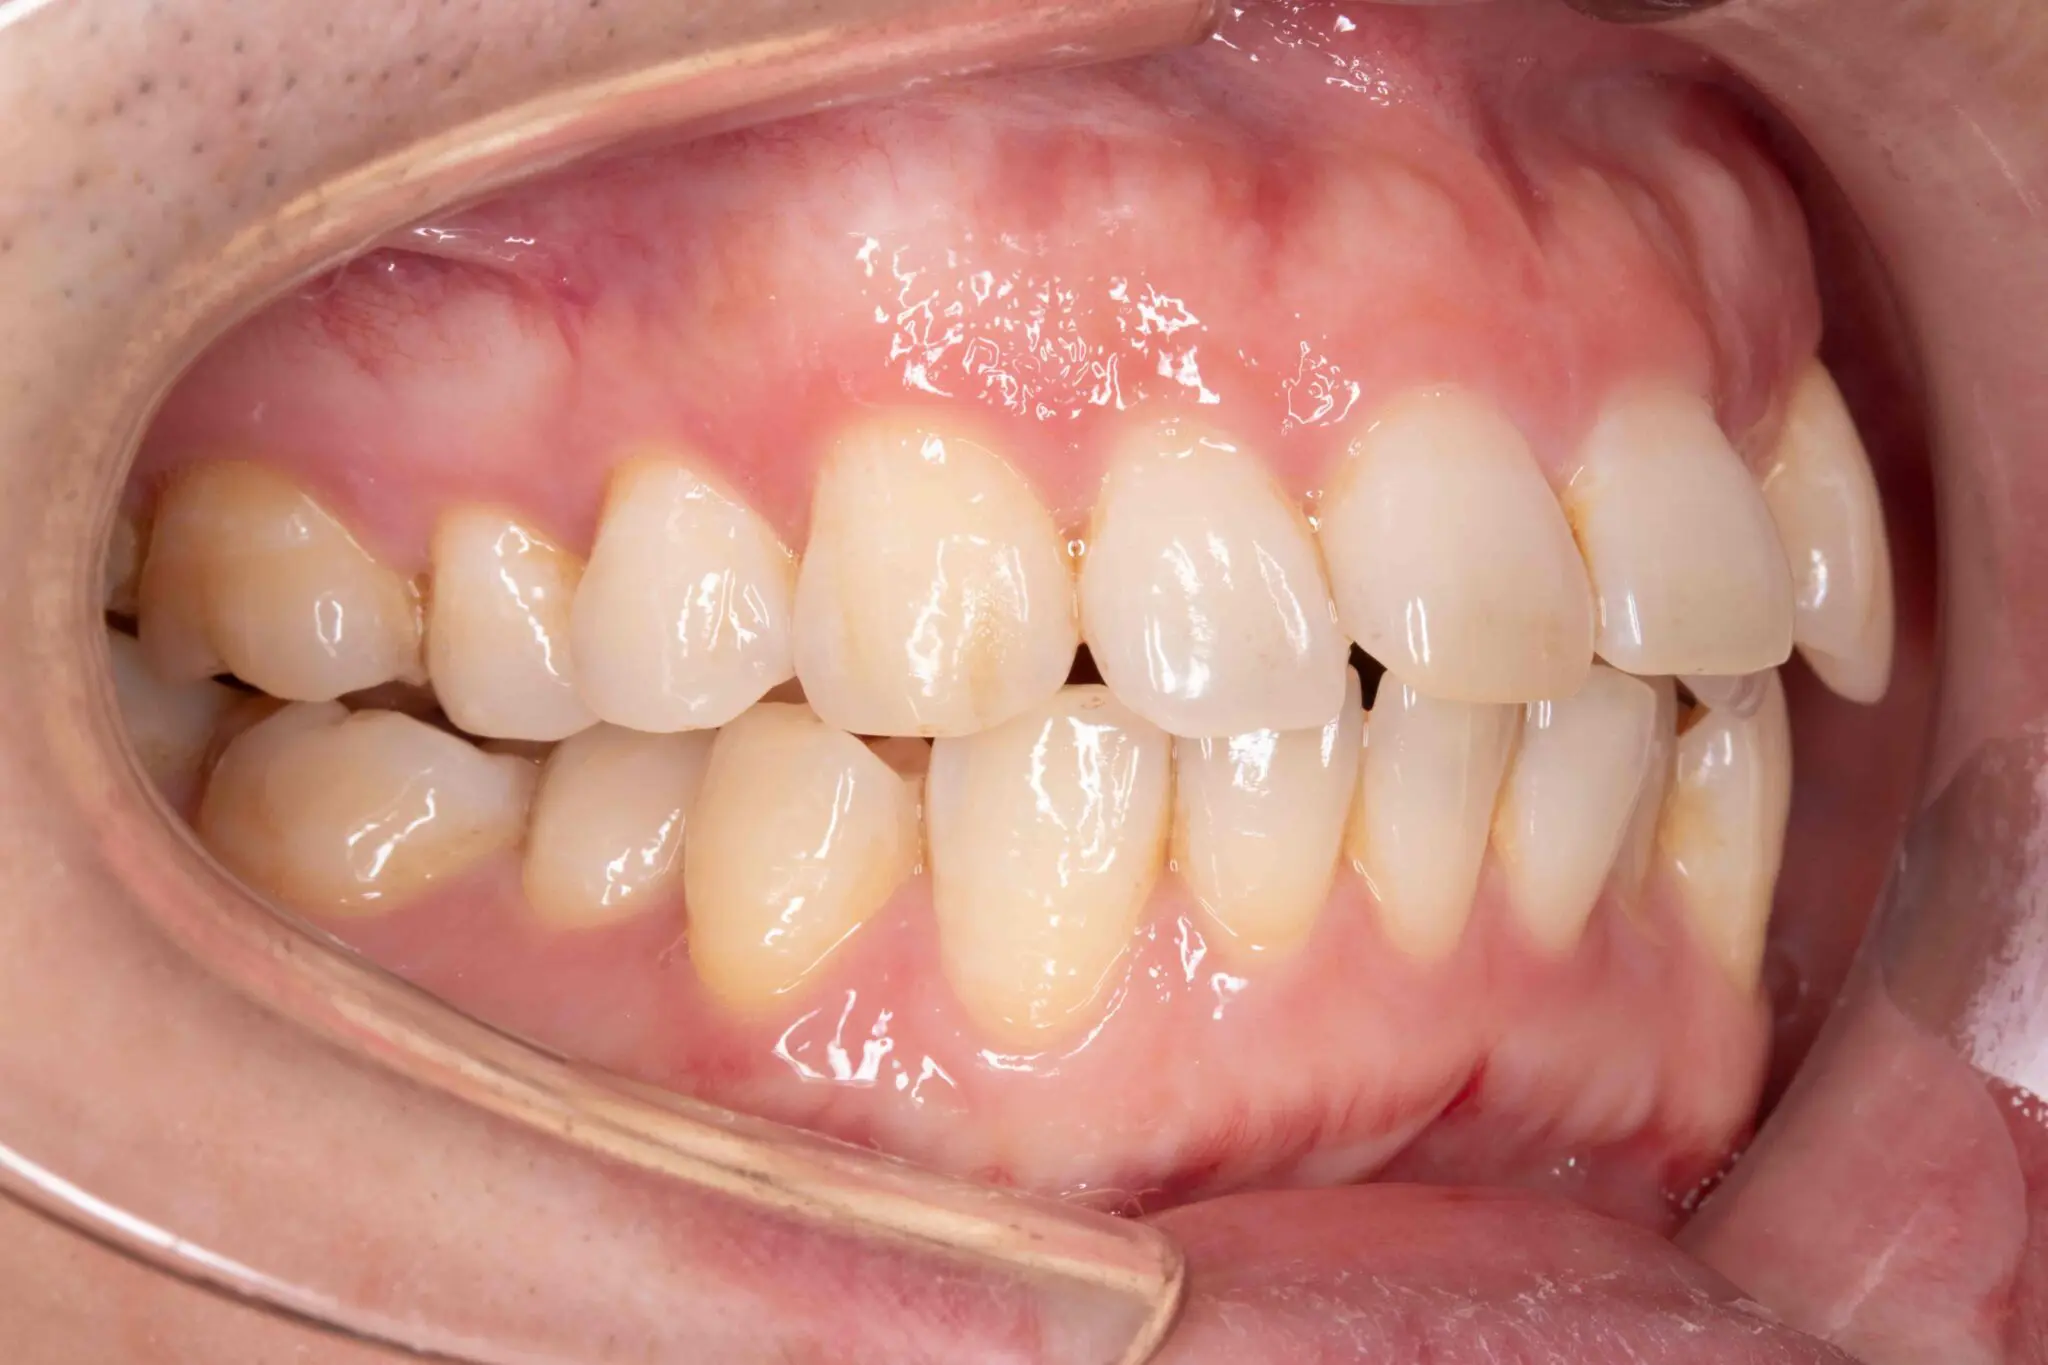

Before

After